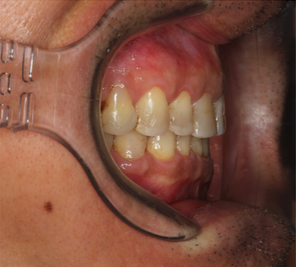

Mr NK, a 52-year-old male, presented with concerns of gradually shortening teeth and sensitivity to cold drinks. He also reported feeling self-conscious about his smile in photos. He is medically fit and has been using a night guard for his sleep-related grinding habit for the past year. Clinical examination revealed moderately worn dentition from erosion and attrition, along with mild crowding of the lower anterior incisors.

Intra-Oral Pictures (Before)

- Erosion severity: ACE Class Class III

- Reduced occlusal vertical dimension

- Mild crowding of lower anterior teeth